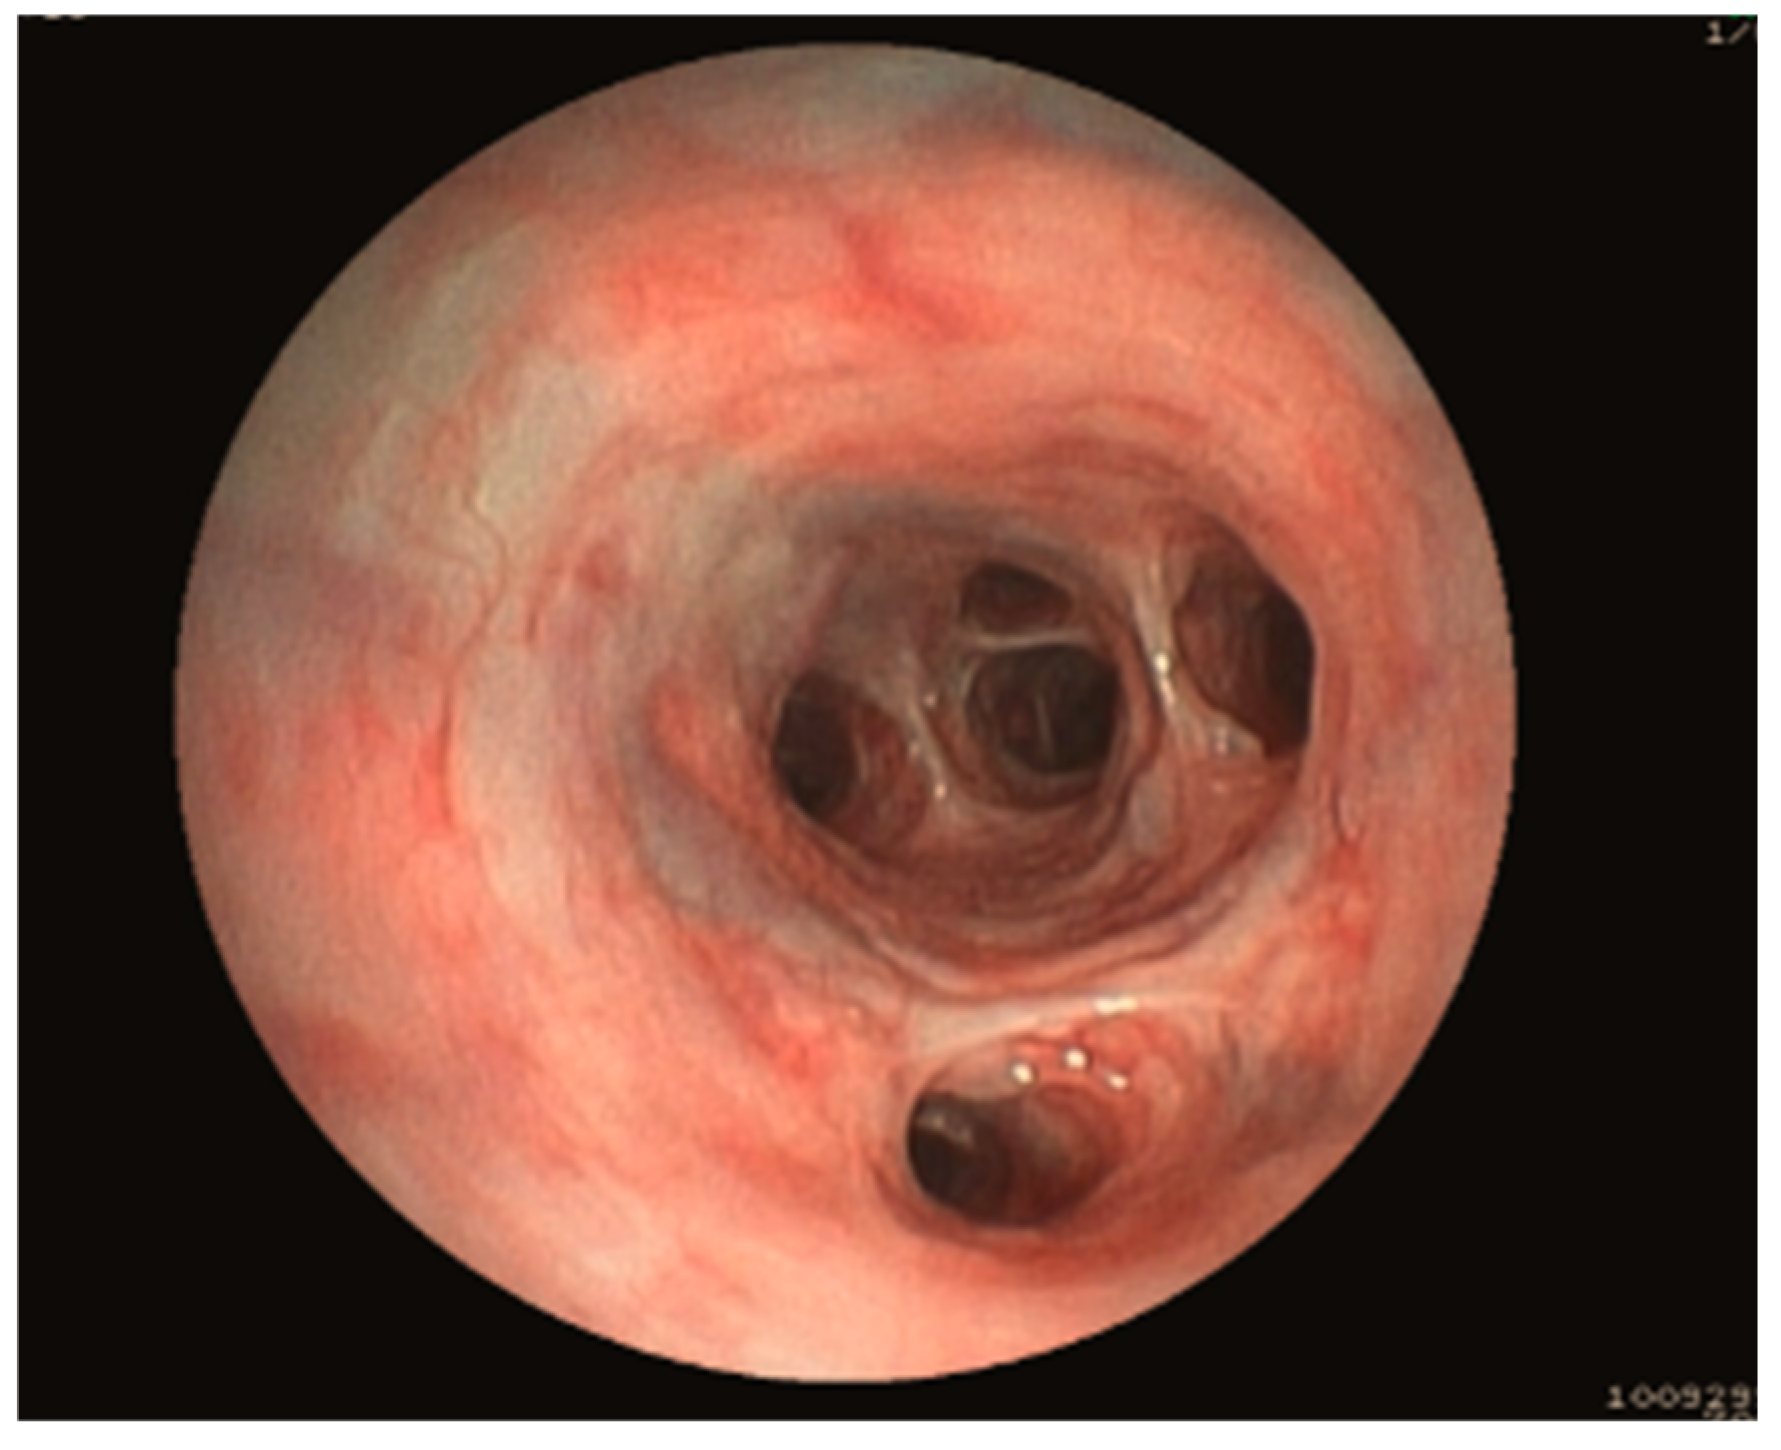

2.2. Bronchoscopy

3.1.1. Group Allocation Based on Bronchoscopy

3.1.5. Bronchoscopy Findings